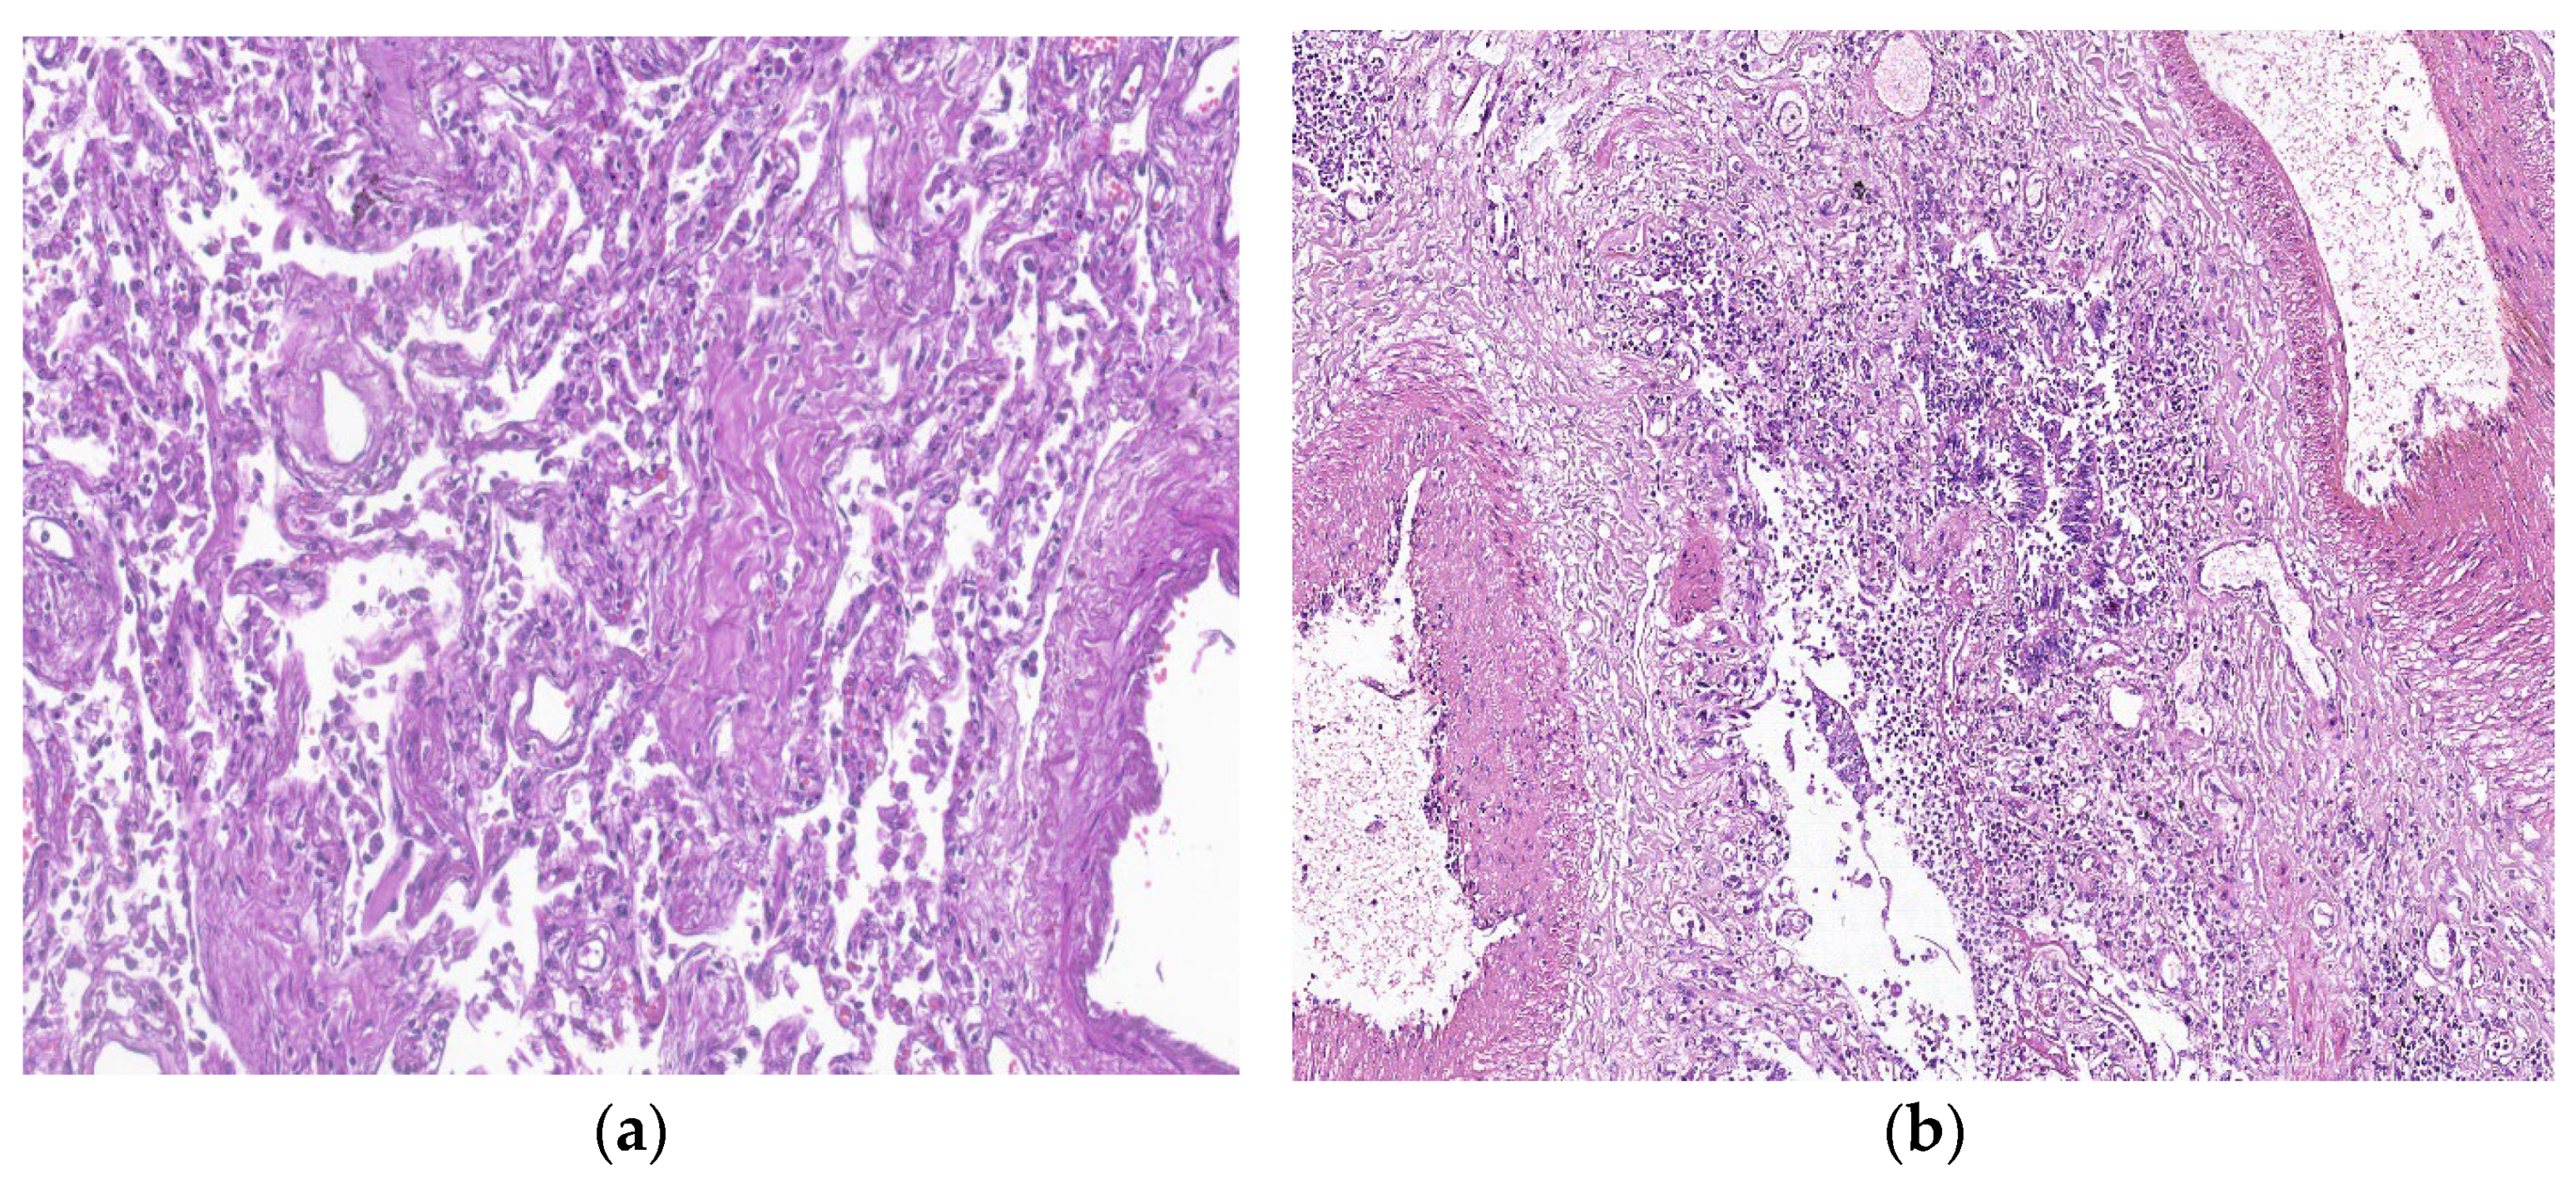

7. Histopathologic Characterization